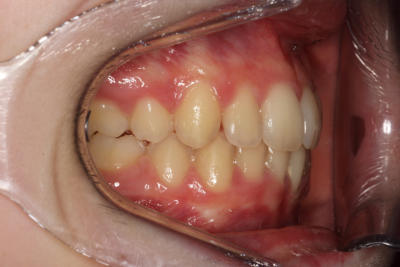

Crowding – Child case